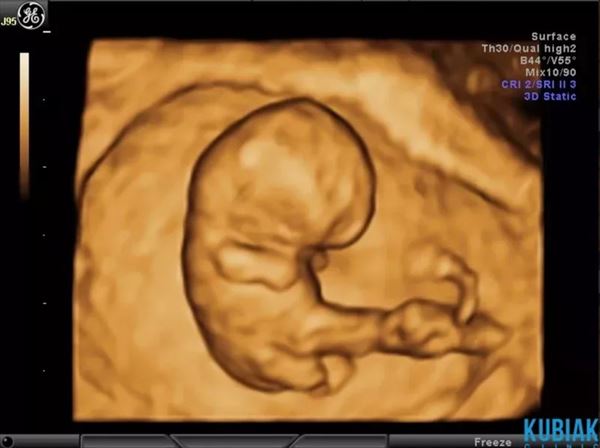

Kobietom w ciąży zapewniamy opiekę przez cały okres jej trwania. W tym celu przeprowadzamy badania ultrasonograficzne, podczas których sprawdzamy, jak rozwija się płód i oceniamy płyn owodniowy oraz łożysko. Kontrolujemy również przepływy naczyniowe u płodu i matki, wykorzystując do tego aparaturę dopplerowską.